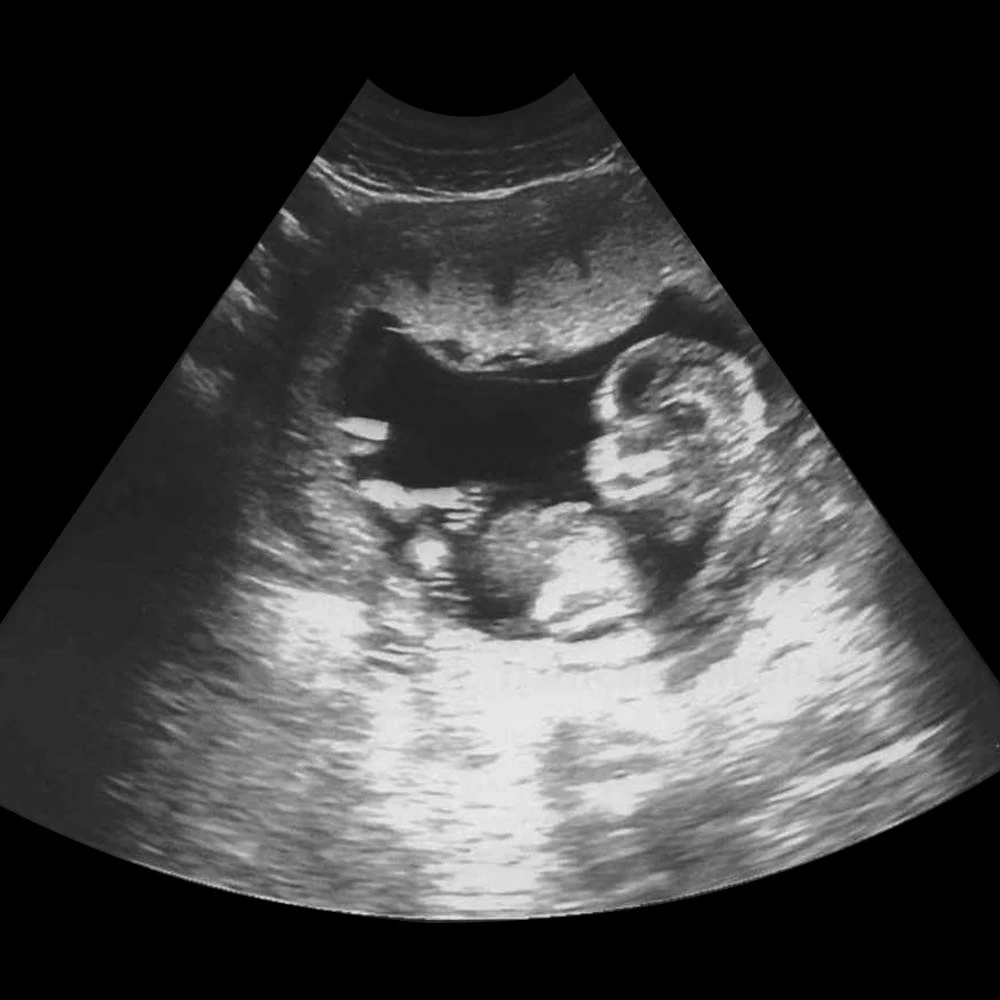

На четырнадцатой неделе при хорошем чувствительном аппарате УЗИ уже можно определить пол ребенка.

На 22 неделе размеры плода увеличиваются до 28 см, вес – до 450-500 грамм. Размеры головки становятся пропорциональны туловищу и конечностям. Ноги практически все время находятся в согнутом состоянии.

К концу этой недели масса плода увеличивается до 600 грамм, длина тела – до 30-32 см.